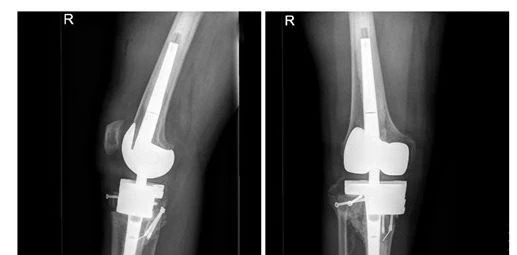

膝关节置换术后

8月22日,关振鹏主任带领骨关节团队为陈先生首先实施了右下肢关节置换手术。手术历时近3个小时,非常成功。手术的成功让陈先生获得了与原来等长并且没有内翻畸形的右下肢,术后恢复良好。